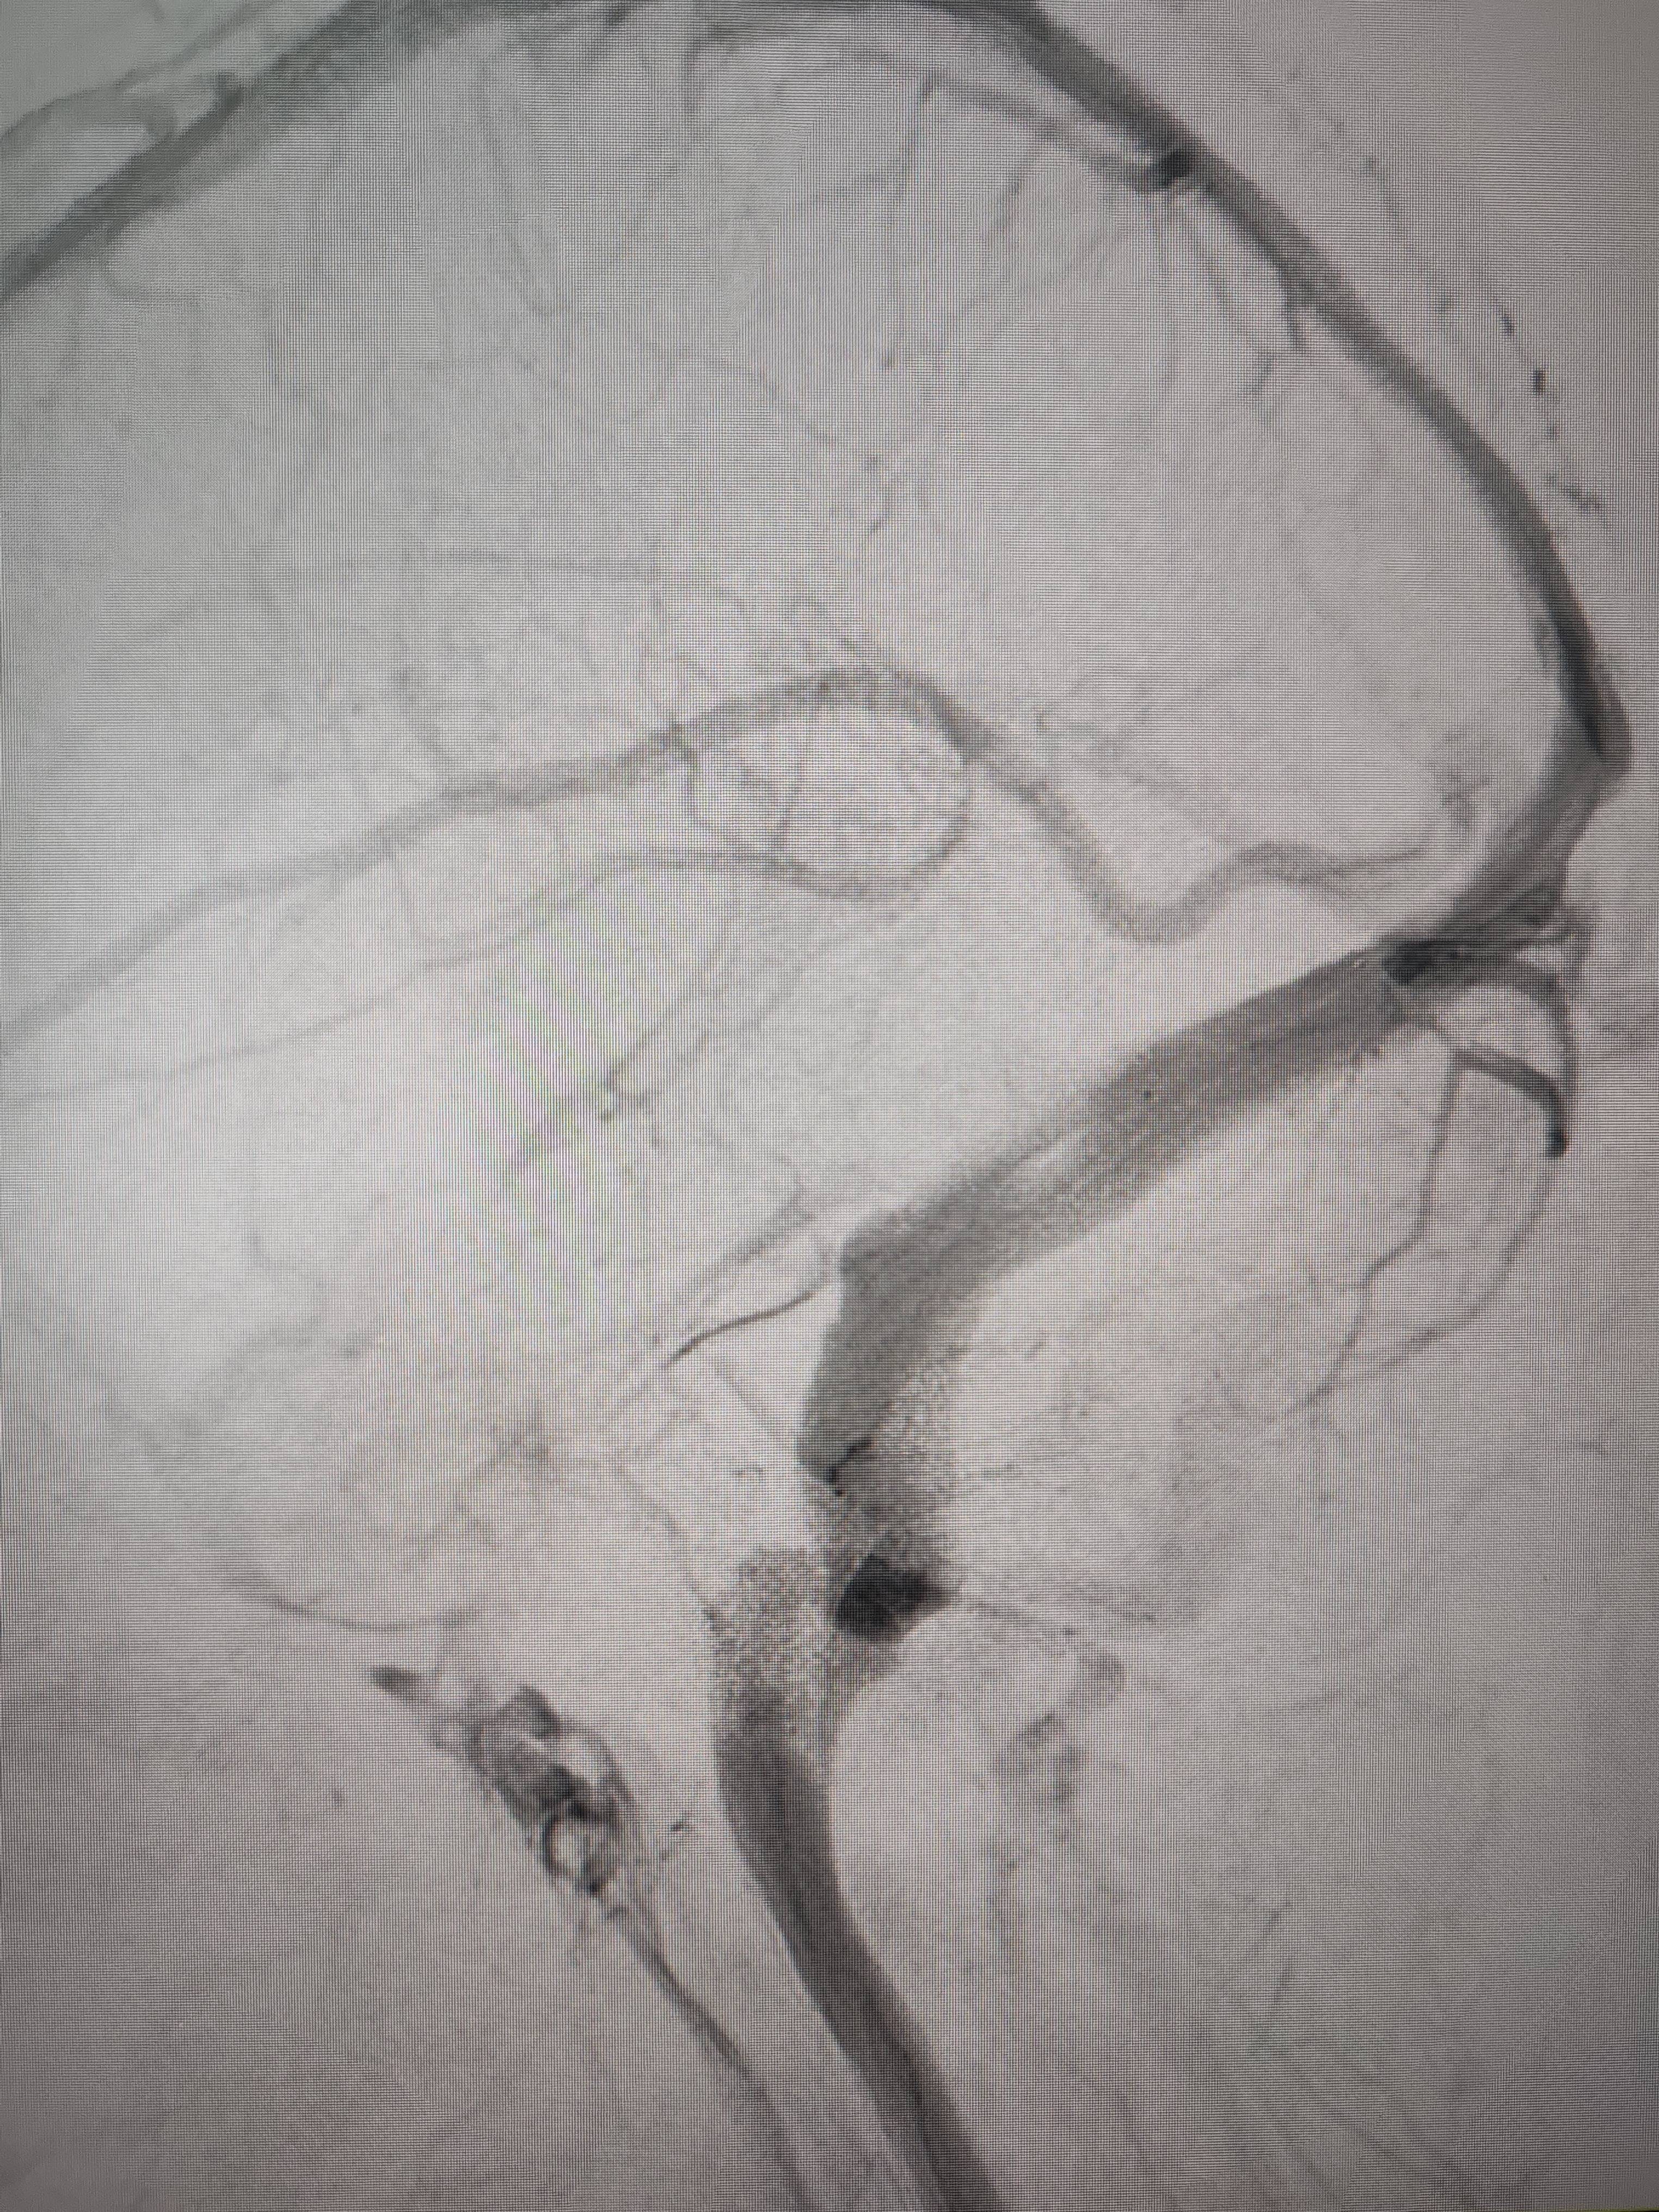

患者造影图像显示,其耳侧静脉窦狭窄。 南方+ 欧阳少伟 拍摄

李宝民举例说,通过查体、CT、造影等影像技术的检查,患者赵女士是由于静脉窦狭窄,导致缓慢的静脉血流也出现“湍流”现象,其拐弯、打漩涡、回流产生的声响,又顺着骨传导,传至耳蜗处,进而让患者出现搏动性耳鸣的症状。